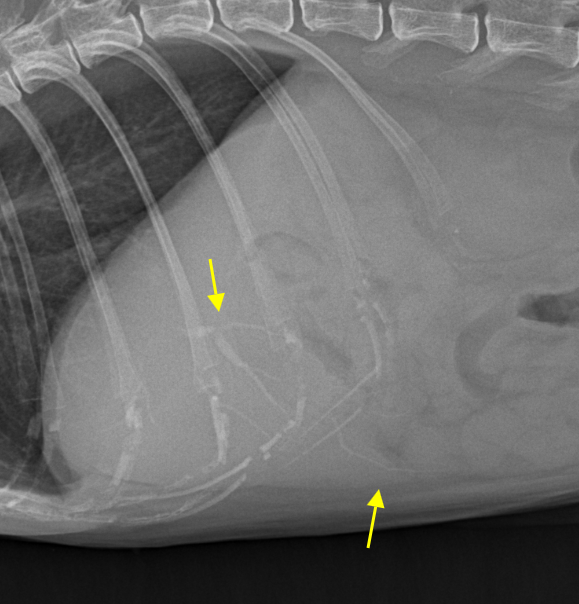

feline intrahepatic bile calculi : radiography

ultrasonography